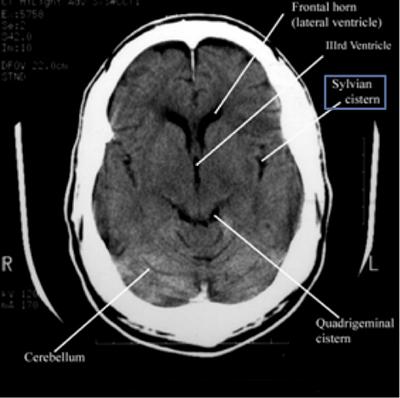

Step 2: Cisterns

Cisterns

Cisterns are the compartments within any of the openings in the subarachnoid space of the brain filled with cerebrospinal fluid. Two key questions to answer regarding the four key cisterns (Circummesencephalic, Suprasellar, Quadrigeminal and Sylvian)

• Is there blood?

• Are the cisterns open?